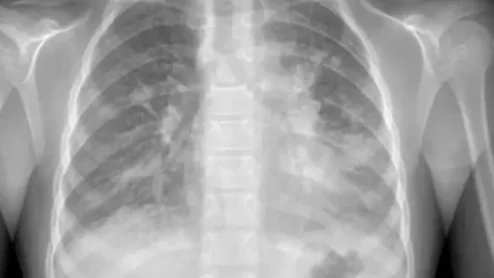

Following a recent surge of mycoplasma pneumoniae pneumonia cases, experts have issued new guidance to help providers quickly identify and treat the condition, with imaging playing a prominent role.